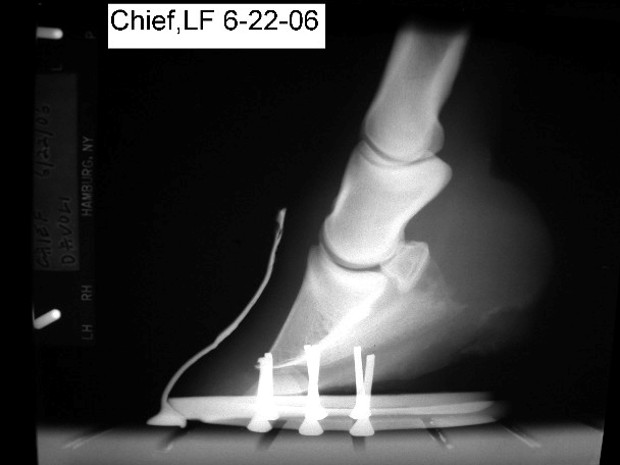

i am attaching xrays and photos of his left front. xrays are from 10/05 and 6/06. photos are from 6/06.

Certainly many of the problems you describe are related to the conformation of the front feet and if I understand your post properly I disagree with your veterinarians assessment of the degree of rotation of the coffin bone in each of the radiographs above. He is apparently drawing a line from the proximal wall rather than looking at the distal wall or the relationship with the ground. I would calculate the difference of the measured angle of the bottom of the coffin bone with a more normal 6 degree tilt and call that the degree of rotation.

Here is the problem: is this rotation because of past founder or because of primary flexor contracture (ie club feet). The two will look similar at this point though the upright pasterns may tip the scales a bit to flexor contracture. If it is decided it is the former, much can be done to return these feet to normal. It it is the latter we are stuck with this.

No I am not saying it is 6 degrees of rotation but by using the normal tilt of 4 to 6 degrees and subtracting the measured angle you can get a truer picture of the amount of rotation you have. And not the trim so much responsible as past founder vs DDF contracture. Though I lean toward the latter for the reasons given above.

I guess he believes this is due to flexor contracture which will not respond to lowering the heels. However I have seen dozens of horses derotated following founder episodes and we have many reports of it on these boards. I have to say his attitude does leave me nonplussed but if your problems are the result of flexor contracture, he will be mostly correct about this horse but his lack of attention to the flare in a tripping horse and the obvious lack of heel support, both evident in the radiographs, are areas that could be addressed in any case in my opinion. I will be interested to hear the second opinion and I want you to develop an open mind to both possibilities however. If you go doing remarkable heel lowering and their is no room for flexor stretching/relaxation you will have to nurse this foot back to its current conformation.

The feet do look better valerie, but if the horse is lame from the shoeing it suggests we may be doing something wrong. It is important to try and localize the lameness. The radiographs and the manner in which the heels were lowered suggest that soreness is coming from excessive thinning at the sole of the toe. It appears the farrier lowered the heels by cutting a wedge that extends from the heel to the toe. I spent years making horses sore by doing that. Instead a wedge taken from the heels to the quarters, then rotating the sole of the toe off the ground gives better results. On the other hand if the horse is landing flat on this it does suggest we have the room to improve this horses angles. See the article on derotation for pictures of this.

now reality check. i am posting the xrays of his rf taken the same days as his left. this is what my vet calls roughly 0 rotation... does that look right to you? it was at roughly 5 degrees three years ago. i think at this point that he is possibly a little sorer now on his right. he does have a head bob, my instint is its his right foot, but i could be wrong. he is still toe walking on his right. at this point, i am proud of myself for not going into a panic! this is actually to be expected while we work out the kinks of this trim?

rf

I think lowering the heel a touch on both sides has reduced the hyper flexion of the coffin jt some and therefore it does not push forward as much. It is improved. Assuming the lameness resolved, I do think next trimming and shoeing the last of the flare might be removed and I think I would also consider a bit more rocker in the shoe. However the coffin bone remains upright with respect to the ground and though once all the flare is removed the coffin bone will be parallel with the front wall, no rotation with your vets definition, the coffin bone will still be rotated with respect to the ground when compared with other horses. As happens with digital flexor contracture it is the whole hoof that is rotated.